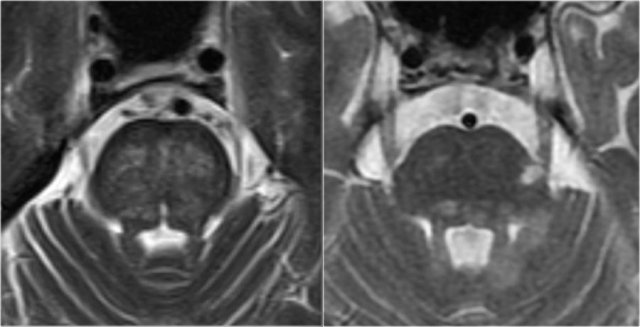

This is a coronal T2 image of a brain specimen with MS involvement. The lesions in the deep white matter (yellow arrow) are nonspecific and can be seen in many diseases.

Typical for MS in this case is:

- Juxtacortical lesions (green circle) - touching the cortex (no intervening WM)

- Periventricular lesions – in direct contact with the ventricles

- Involvement of the corpus callosum (blue arrow)

- Involvement of the temporal lobe (red arrow)